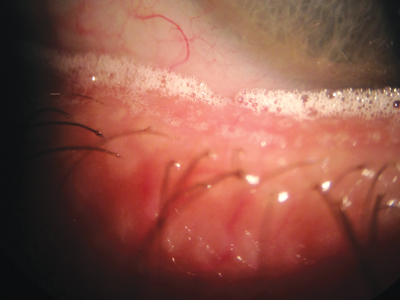

Figure 2: ‘Champagne bubbles’ along the lower lid margin characteristic of MGD.

Lid hygiene is a major topic in itself, especially the vexed question of the role of baby shampoo. Crusty eyelash deposits, collarettes in particular, are strongly associated with colonisation of the lash follicles by the arthropod mite, Demodex folliculorum, which are best observed with a slit-lamp using 40x magnification.